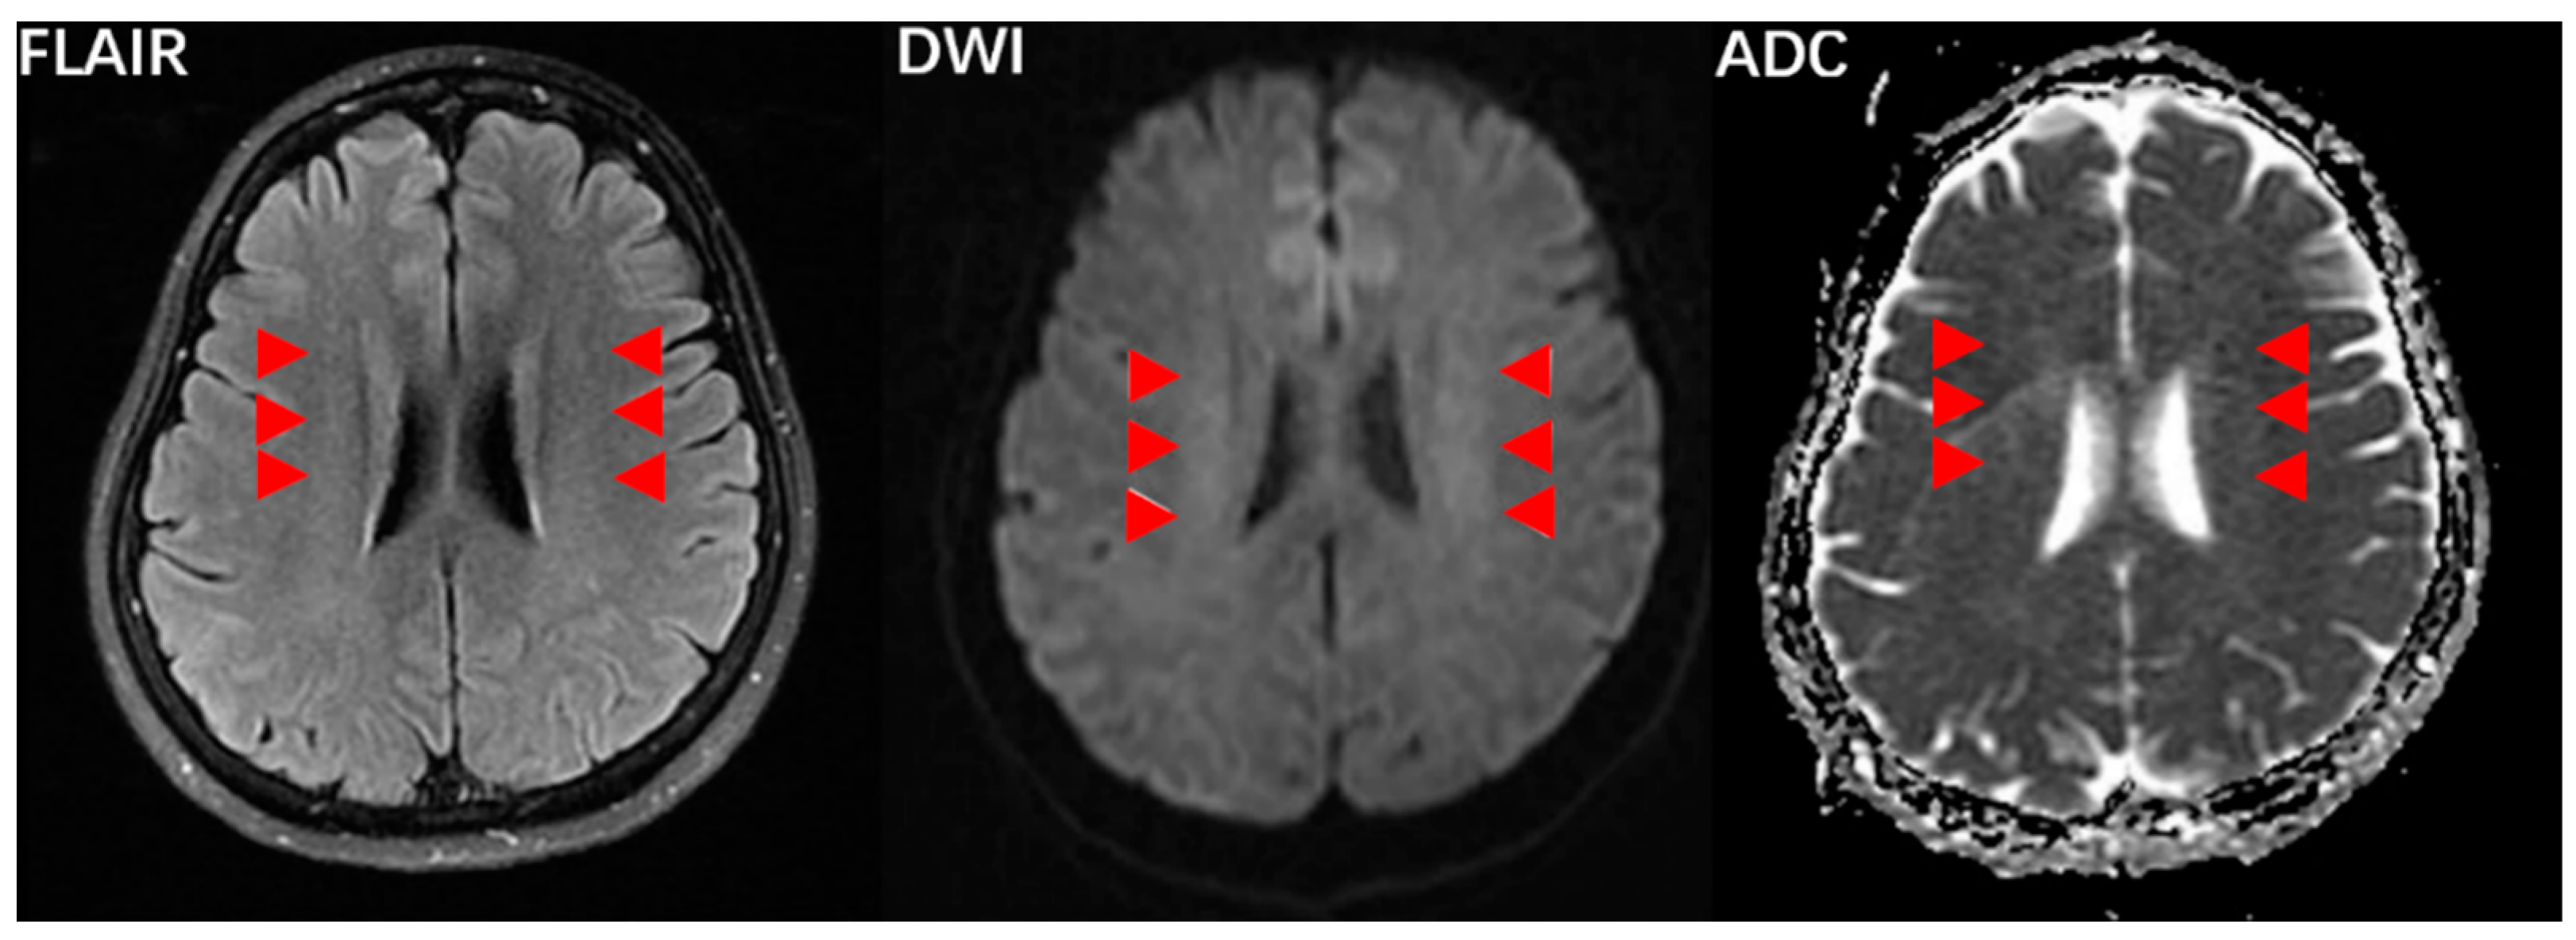

3.3. CVOD-Associated Anxiety and Depression and WMLs

4.2. CVOD-Related WMLs

4.3. Cerebral Hypoperfusion and CVOD-Associated Anxiety and Depression